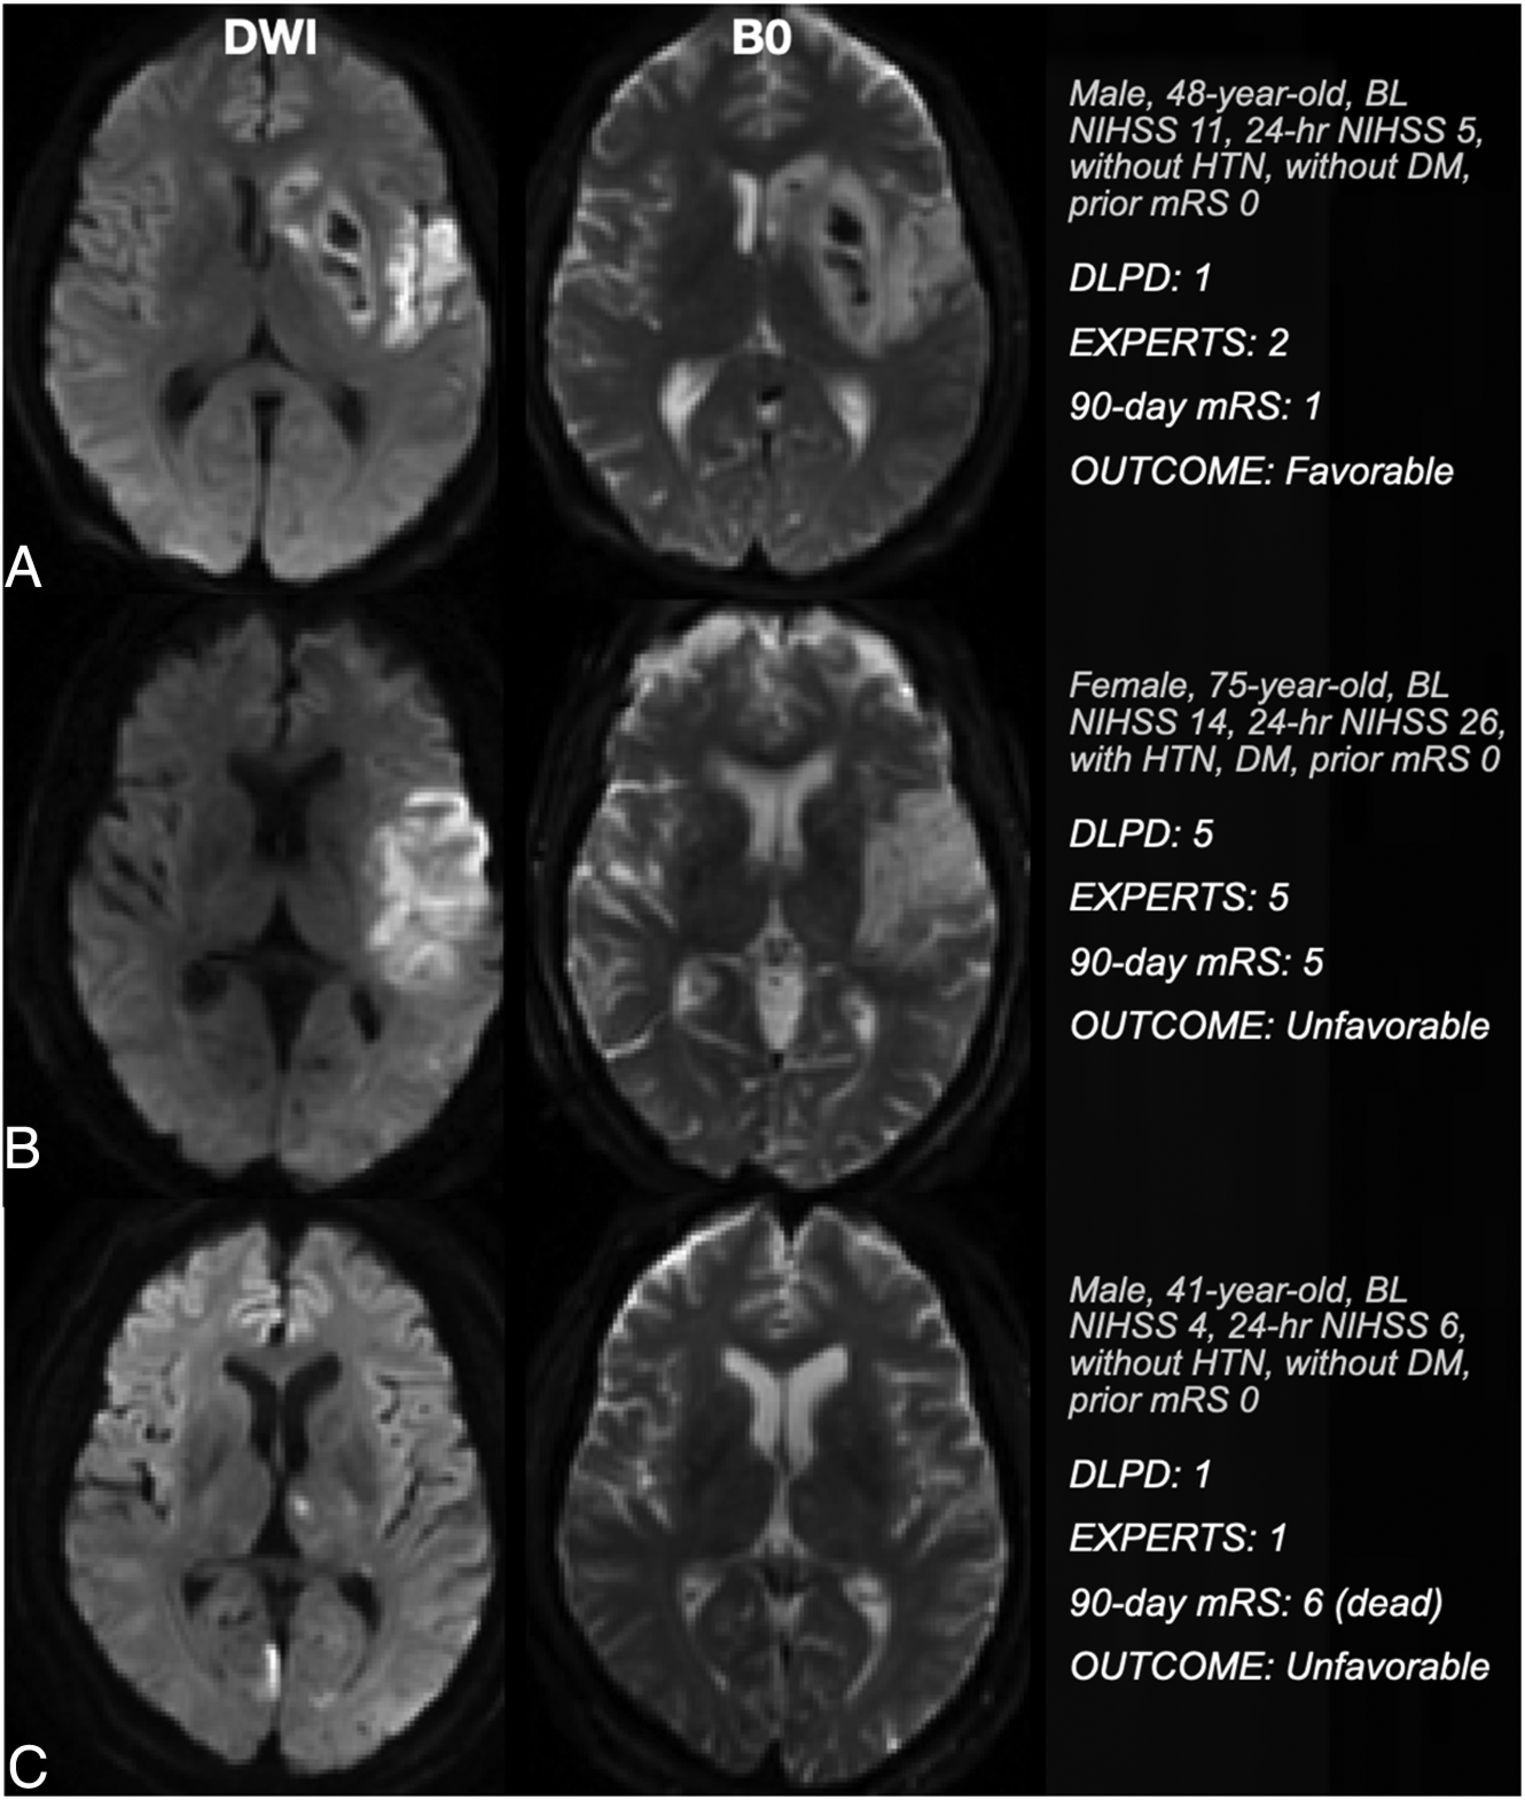

Table 3 compares the DLPD model and the consensus of clinical readers across multiple metrics. The DLPD model had improved values in all evaluated metrics, achieving a Gwet AC of 0.79 (95% CI, 0.71–0.86), an MAE of 0.89 (95% CI, 0.70–1.11), ±1ACC of 81% (95% CI, 73%–90%), and an ACC of 36% (95% CI, 26%–46%). The level of agreement among the 5 clinical readers, as gauged by a strong Gwet AC of 0.83 (95% CI, 0.80–0.86), affirms the consistency in their judgments and justifies the use of a clinical consensus score to compare with the DLPD. The clinical consensus score achieved a Gwet AC of 0.76 (95% CI, 0.67–0.84), MAE of 0.95 (95% CI, 0.75–1.17), ±1ACC of 79% (95% CI, 70%–88%), and ACC of 36% (95% CI, 25%–46%). Noninferiority tests confirmed that the performance of the DLPD model was noninferior to that of the clinicians across all evaluated metrics, except for ACC. The significant P values were P < .001 for the Gwet AC, P = .02 for MAE, and P < .001 for ±1ACC, while the P value for ACC was not significant (P = .07). Figure 2 presents 3 illustrative examples of outcome predictions made by the DLPD and physicians.

MR images (the first and second columns represent DWI and B0 images, respectively) for 3 patients with diverse clinical histories and 90-day mRS scores. Patient A is a 48-year-old man with a baseline NIHSS of 11, 24-hour NIHSS of 5, and a 90-day mRS of 1. He has no medical history of either diabetes or hypertension. The DL model accurately predicted his score. However, the readers overestimated his score by 1 point. Patient B, a 75-year-old woman, has a medical history that includes diabetes and hypertension and a 90-day mRS of 5. Both the DL model and the readers accurately predicted her 90-day mRS score of 5. Patient C, a 41-year-old man with no history of diabetes or hypertension, has a 90-day mRS score of 6. However, both the DL model and the readers incorrectly predicted his 90-day mRS score as 1. HTN indicates hypertension; DM. diabetes mellitus.